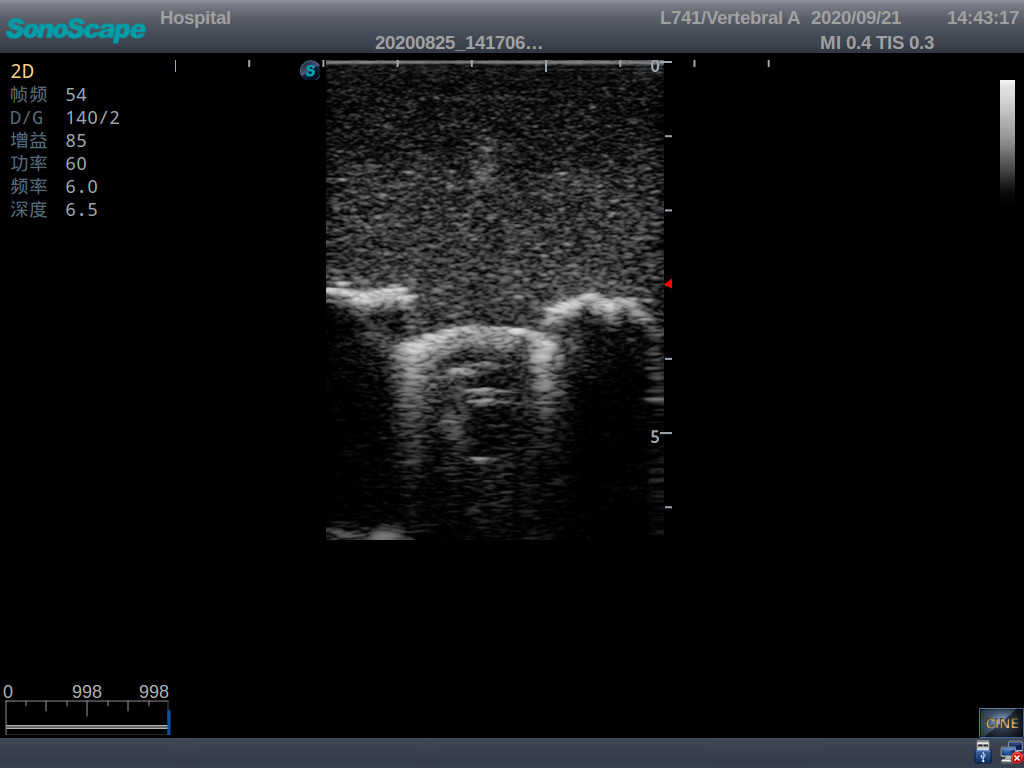

Pediatric Lumbar Puncture Ultrasound Training Model

This model is an ideal choice for ultrasound-guided pediatric lumbar puncture training with true-to-life skin feel and touch, accurate anatomical structures as well as real clinical ultrasound images. Realistic resistance to needle tips and correct landmarks provide excellent hands-on experience.

Accurate anatomical structure of L1-L5 and the vertebral canal

2)  Real clinical ultrasound images

1)  Ultrasound-guided lumbar puncture practice